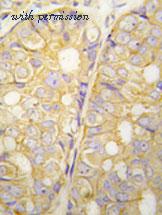

- domestic rabbit polyclonal

reactivity: human

application: western blot, immunohistochemistry, immunohistochemistry - paraffin section

gene information - human POTE

- description:POTE ankyrin domain family member D